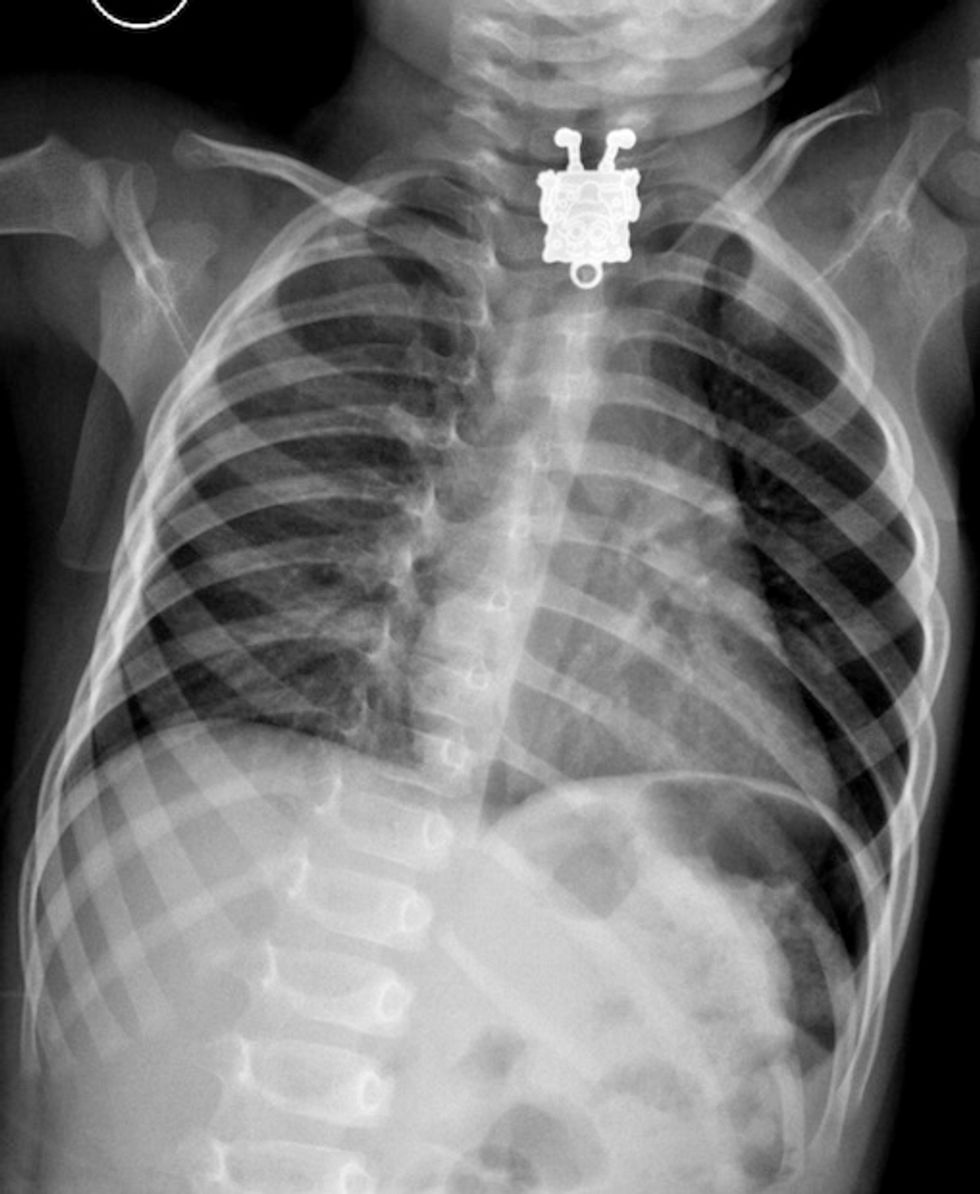

Case courtesy of Dr Ghofran Ageely, Radiopaedia.org

One 16-month-old boy in Saudi Arabia recently swallowed his sister's SpongeBob necklace and was rushed to the hospital. The X-rays of the child's chest taken at King Abdulaziz University Hospital in Jeddah produced some entertaining images. Including one that showed the popular cartoon character smiling at them while sticking out his tongue.

The Daily Mail reported radiologist Dr. Agreely actually screamed when she first saw the image on the scan.

Doctors were able to retrieve the pendant from the young boy's throat and esophagus and send him home.